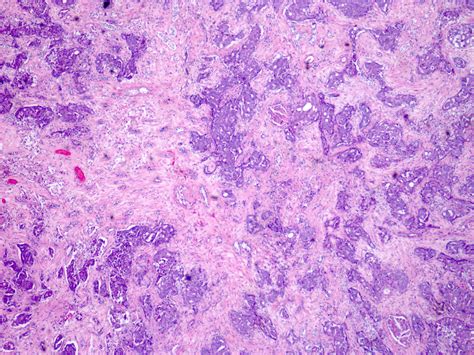

Another condition that affects the function of kidney medulla is acute tubular necrosis, which is characterized by the death of renal tubular cells. This condition can occur due to ischemia, nephrotoxins, or sepsis, leading to the loss of the kidney's ability to concentrate urine and maintain electrolyte balance. Acute tubular necrosis can result in acute kidney injury, requiring prompt medical intervention to prevent further damage.